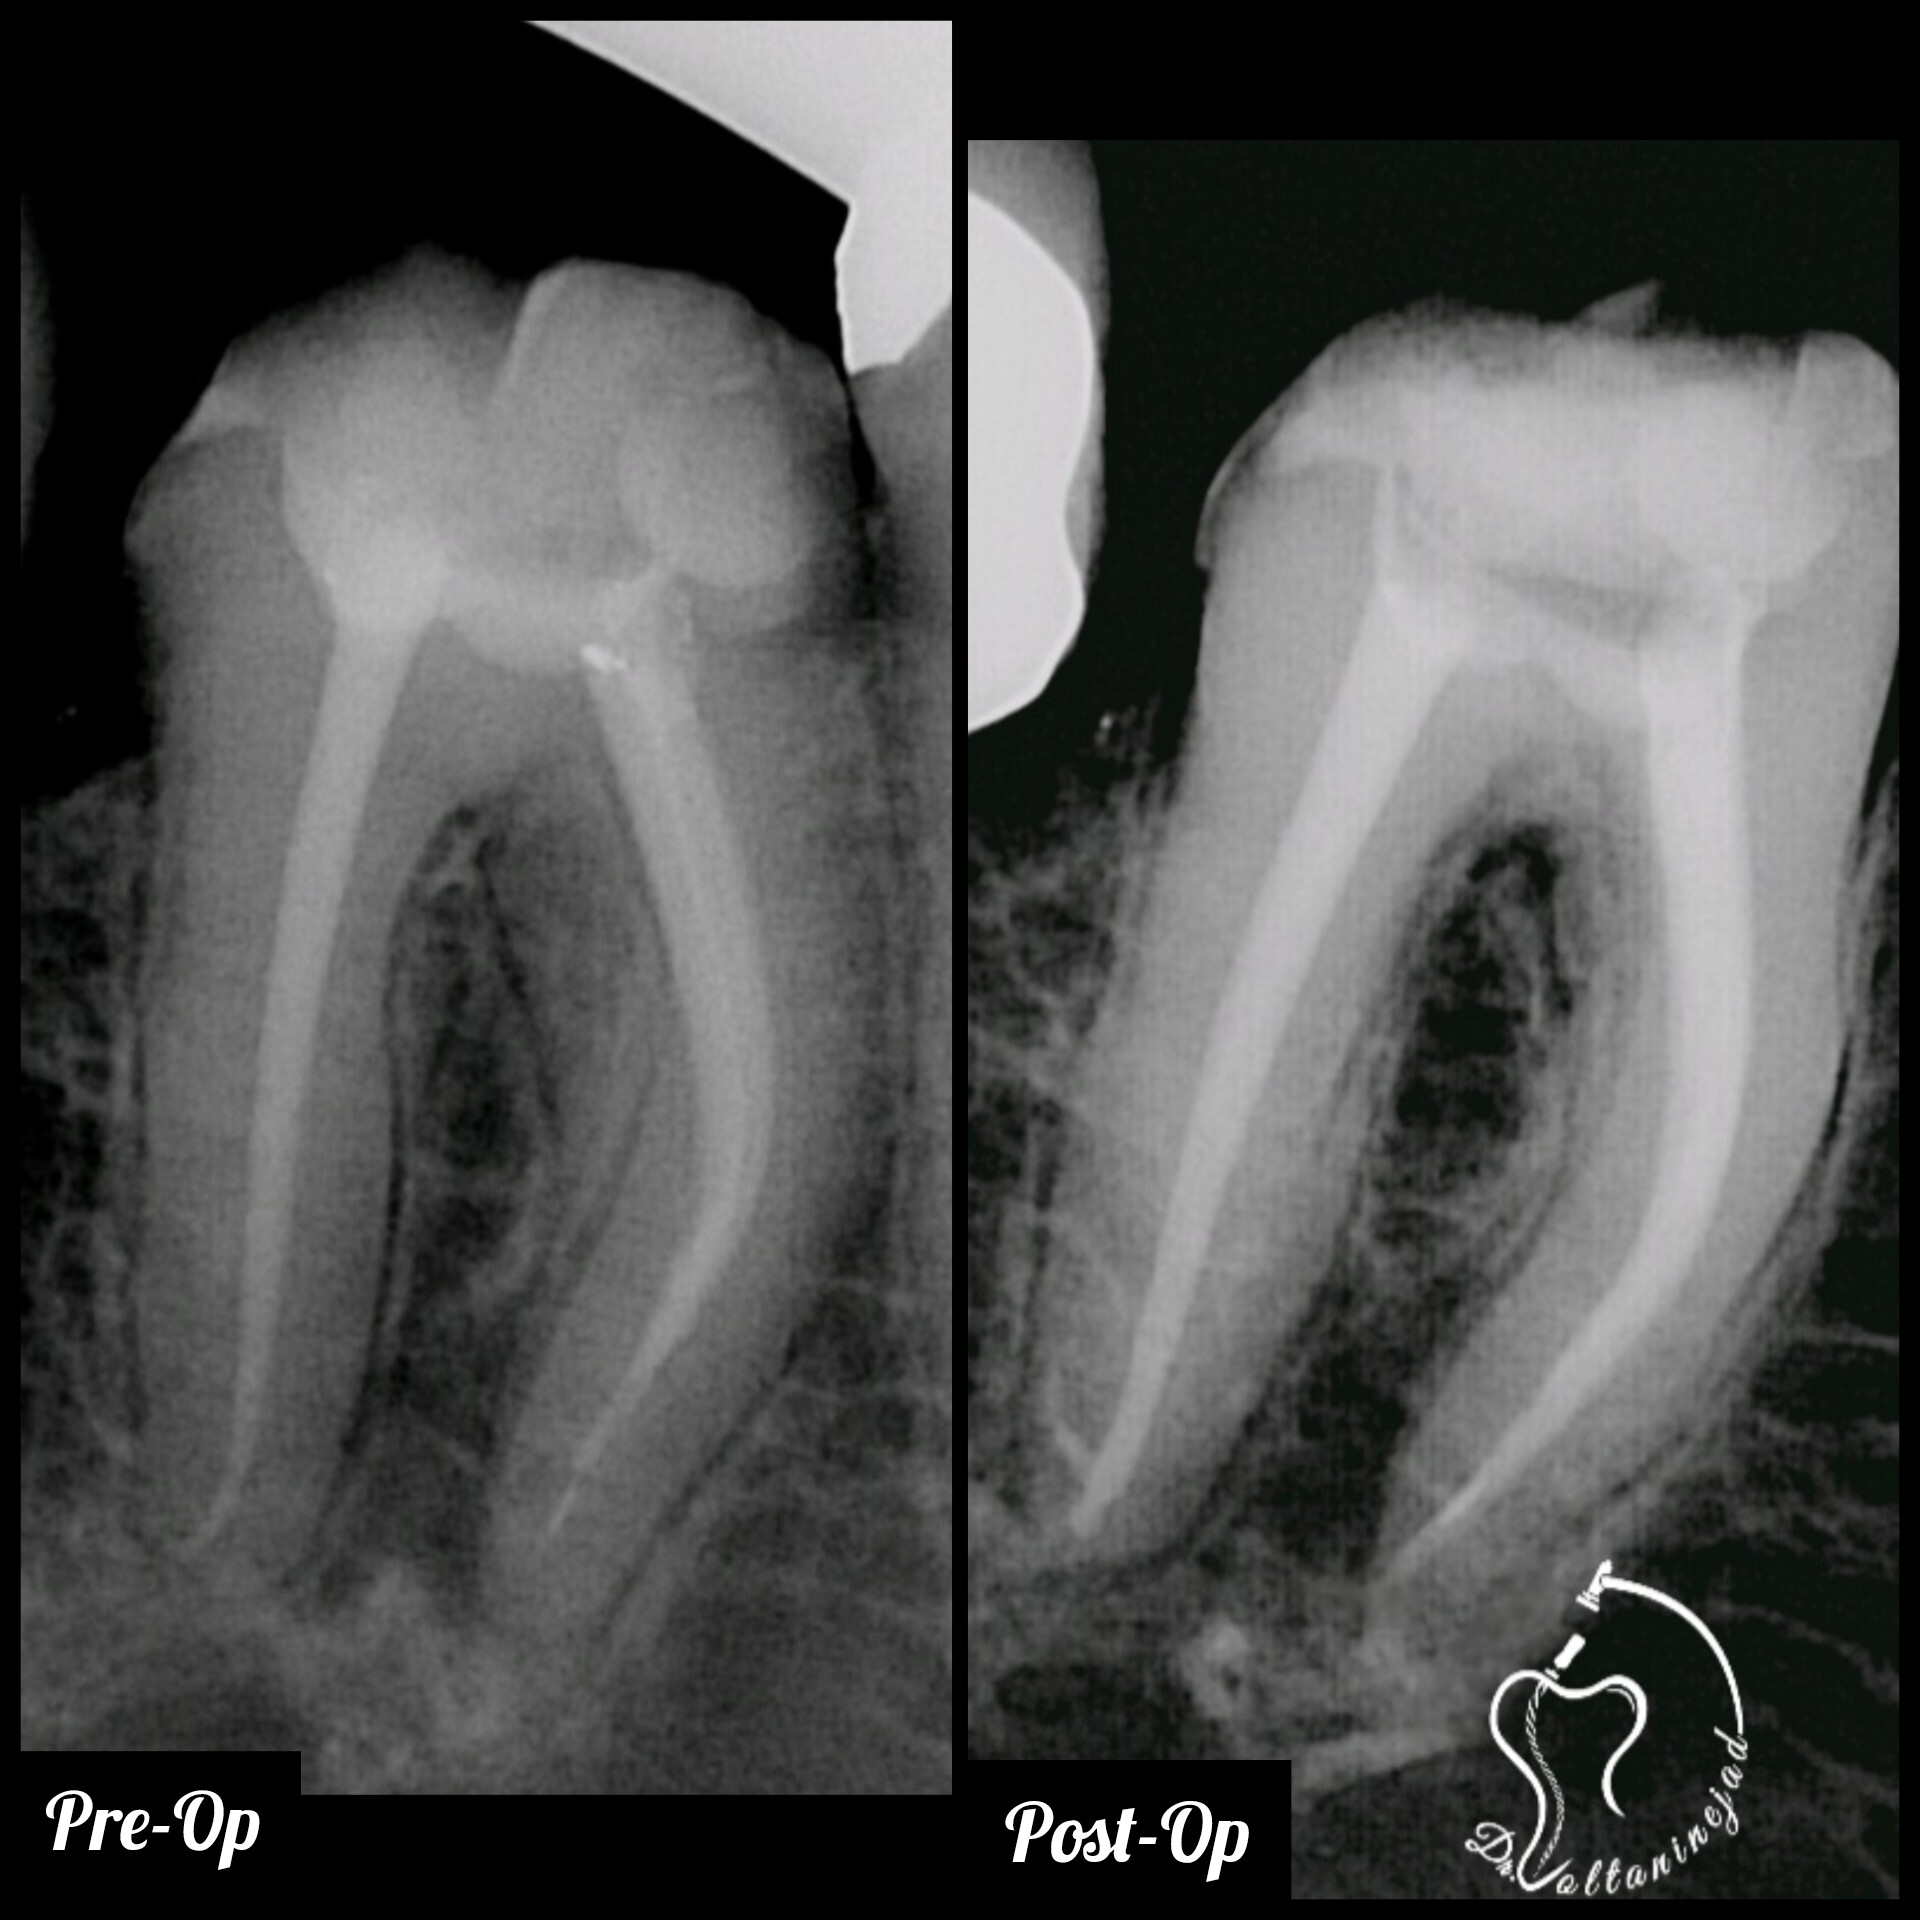

🔹 درمان ریشه دندان کانین با ضایعه وسیع

• شرح کوتاه: بیمار با درد و تورم شدید مراجعه کرد. پس از درمان ریشه تخصصی، ضایعه استخوانی طی ۶ ماه به‌طور کامل بهبود یافت.

• نتیجه: حفظ دندان و بازگشت عملکرد طبیعی.

درمان ریشه دندان کانین